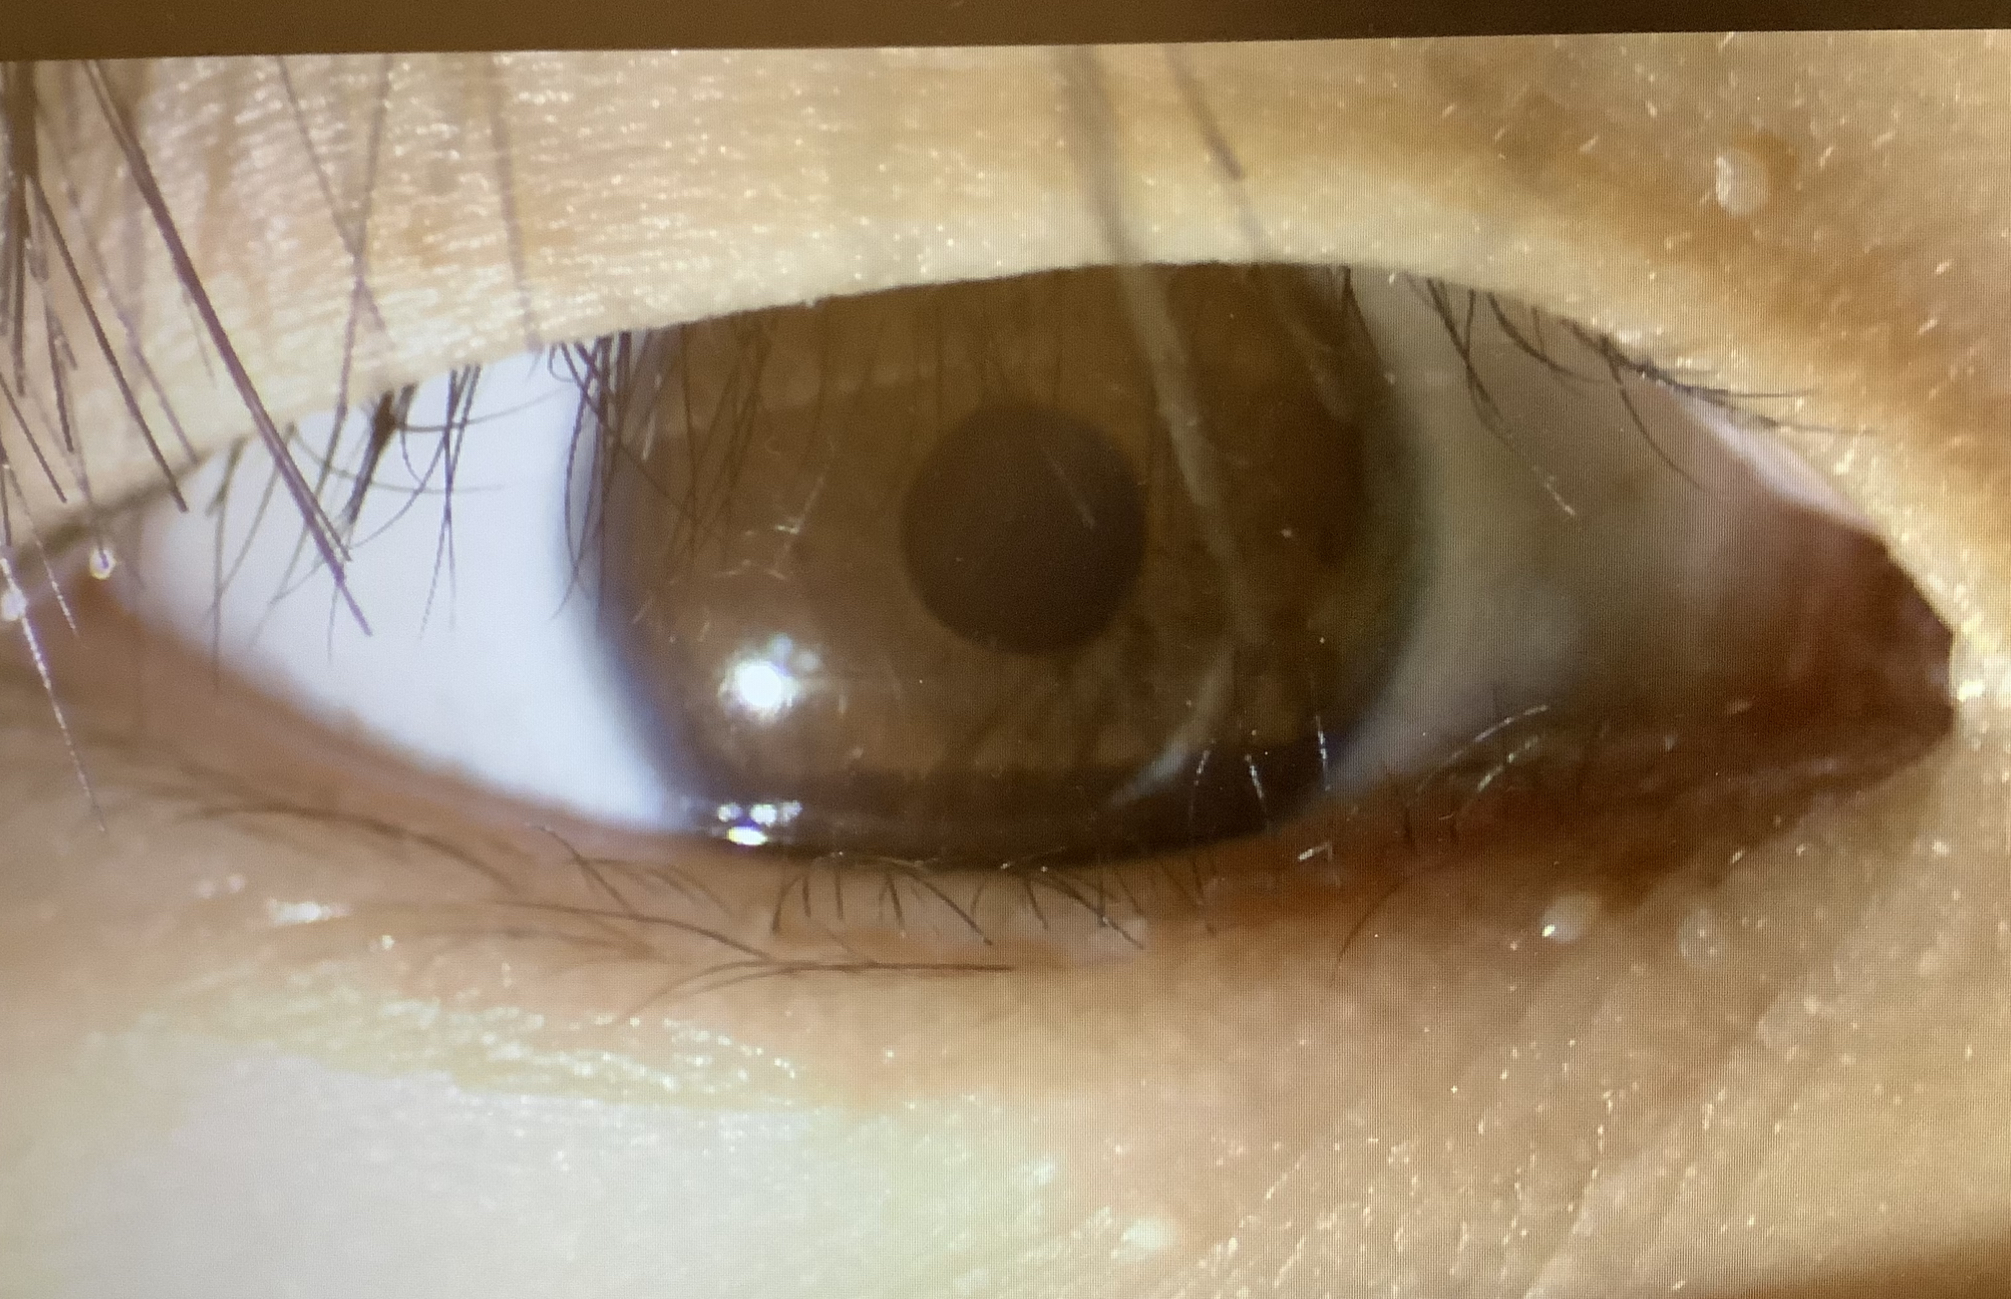

12歳の男の子と15歳の女の子は、まぶたの皮膚量が多く、まつ毛が内側に向いてしまい、眼にあたってしまう“睫毛内反”で、男の子は右の下まぶたのみ、女の子は両方の上まぶたの手術となりました。上まぶたでも下まぶたでも行うべきことは一緒で余分な皮膚を切除し、睫毛が外側に向くようなクセをつけて皮膚を縫ってくるような手術になります。

もう一人は15歳の男の子で、霰粒腫の切開でした。内反症の手術に比べれば楽かもしれませんが、やっぱり緊張したでしょうし、左右両眼で計3個の切開となったので、頑張りが必要だったと思います。でも、よい時期に受診してくれたので、あまり悪い霰粒腫ではなく、まぶたの裏側から切開できたので、キズも残さずきれいに治ってくれるのではと思います。